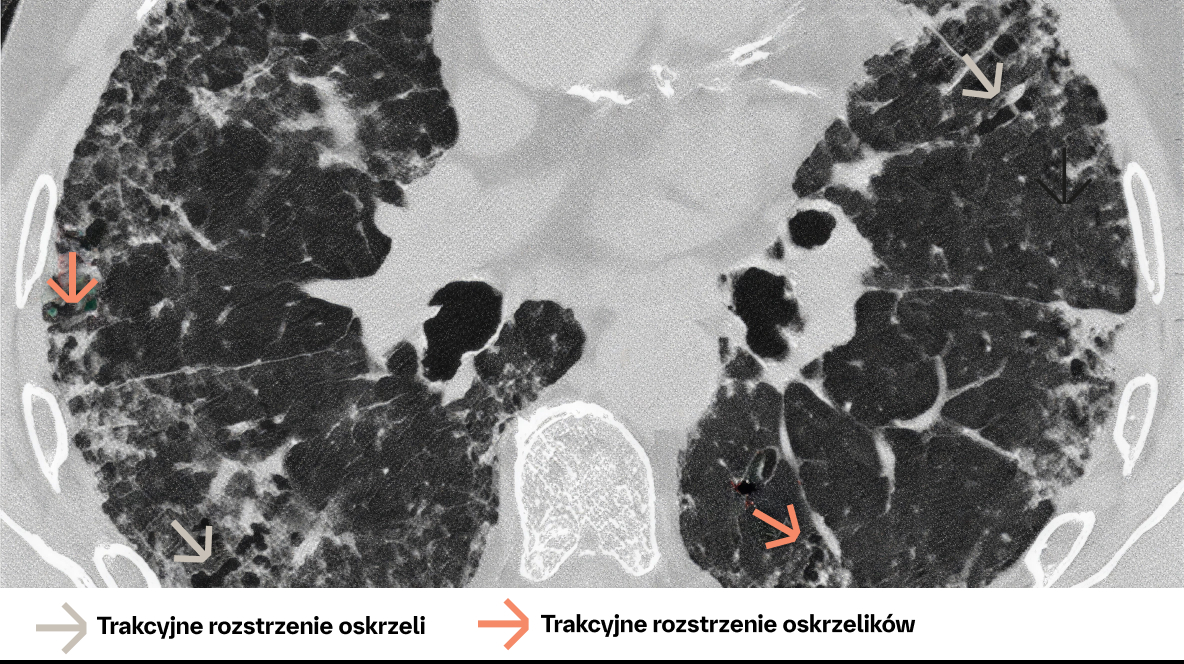

72‑letni mężczyzna z UIP. Badanie HRCT wykazuje rozsiane zmiany siateczkowe oraz trakcyjne rozstrzenia oskrzeli i rozstrzenia oskrzelików.

TRAKCYJNE ROZSTRZENIE OSKRZELI / ROZSTRZENIE OSKRZELIKÓW

Cechy

• Nieprawidłowe i nieregularne rozszerzenie oskrzeli/oskrzelików w wyniku zapalenia dróg oddechowych (czasami odwracalne) lub zwłóknienia płuc

• W badaniu HRCT widoczne jako zwiększenie średnicy dystalnych dróg oddechowych (brak obwodowego zmniejszania się średnicy, widoczność w podopłucnowych częściach płuca w odległości co najmniej 20 mm od opłucnej)

• Na obrazie widoczne są jako rurkowate lub torbielowate przestrzenie powietrzne, w zależności od orientacji oskrzeli na przekroju

• Różnicowanie pomiędzy trakcyjnymi rozstrzeniami oskrzeli a zmianami typu „plastra miodu” jest czasem trudne na przekrojach osiowych. Przydatne są przekroje strzałkowe lub czołowe

Orientacja diagnostyczna

• Trakcyjne rozstrzenia oskrzeli są związane z oznakami włóknienia